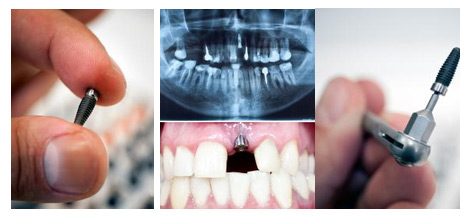

种植牙作为人类的第三幅牙齿,它不仅外观与真牙相似,且拥有与真牙一般的咀嚼能力,这些优点是其他修复方式无法媲美的。虽然种植牙的修复效果非常好,但值得提醒的是选择一家正规的医院进行种植牙很重要。

种植牙对于技术的精度要求很高,这就需要医生既要有进行外科手术的经验,还要掌握口腔修复学的内容。临床上的种植医生必须接受过专门的学习和培训,累积大量临床经验,才能精确完成种植的每一个步骤,确保种植牙的效果。

对于许多种牙患者来说,牙种得好不好还得看效果。好的材料,可保证种植牙效果,终生受用。目前被业内医生使用较多的韩国和欧美的种植体,如韩国Dentium登腾种植系统、韩国osstem奥齿泰种植系统、瑞士ITI种植系统等多种材质,保障手术效果。